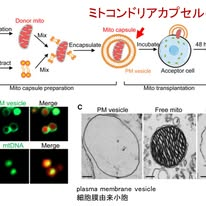

・パーキンソン病を赤血球膜で包んだミトコンドリアで治療する時代が来る!?

***岐阜大学医学部下畑先生の2026年3月23日のFB投稿です***

ミトコンドリアは細胞のエネルギー産生を担う細胞内小器官であり,その機能障害はパーキンソン病やミトコンドリア病をはじめとする多くの神経疾患の病態に関与しています.このため,健常なミトコンドリアを損傷細胞へ補充する「ミトコンドリア移植」は,長年にわたり魅力的な治療戦略として注目されてきました.しかし,分離されたミトコンドリアは不安定であり,標的細胞への取り込み効率が極めて低いという課題がありました.

ミトコンドリアは細胞のエネルギー産生を担う細胞内小器官であり,その機能障害はパーキンソン病やミトコンドリア病をはじめとする多くの神経疾患の病態に関与しています.このため,健常なミトコンドリアを損傷細胞へ補充する「ミトコンドリア移植」は,長年にわたり魅力的な治療戦略として注目されてきました.しかし,分離されたミトコンドリアは不安定であり,標的細胞への取り込み効率が極めて低いという課題がありました.

この問題に対しCell誌に,またも中国から驚くべき研究が報告されました.ドナー由来のミトコンドリアをなんと赤血球膜で包み込み,「ミトコンドリアカプセル」として体内へ投与するという技術です(図1).赤血球膜は生体由来で免疫回避能や血中安定性に優れるという利点がありますが,これをオルガネラ移植に応用した点が革新的です.

具体的には,ヒトまたはマウス赤血球を破砕して得られた膜成分(図1のPM vesicle)と,細胞から抽出したミトコンドリアを混合し,物理的処理を行うことで膜小胞が形成されるそうです.この膜小胞の一部にミトコンドリアが内包されます.これをMito capsuleと呼んでいますが,電子顕微鏡の観察でミトコンドリアの約2倍程度のサイズとなるようです(図1C;矢印).このカプセル化により,ミトコンドリアの細胞内移行効率は飛躍的に向上しました.従来では取り込み効率が5%未満であったのに対し,この手法を用いると70〜80%という高効率で細胞内へ導入されました.

さらに重要なのは,導入されたミトコンドリアが宿主細胞内のミトコンドリアと融合し,機能的に維持される点です.ミトコンドリアを欠損細胞に導入した場合,移植ミトコンドリアは球状から桿状へと形態変化し,生理的なネットワーク構造を再構築することが観察されました.さらに,ミトコンドリア機能障害によって生じる神経変性疾であるLeigh症候群患者由来細胞においてもミトコンドリア機能を回復しました.図2にあるようにATP産生の増加,ミトコンドリアDNA量の増加,変異の低下をもたらすことが確認されています.

さらにin vivo実験においても有効性を示しました.静脈投与されたカプセル化ミトコンドリアは主に肝臓をはじめとする複数の臓器に取り込まれ,機能改善をもたらしました(図3A).Leigh症候群モデルマウスでは平均寿命が約48日から74日へと延長し,明確な生存利益が確認されました.加えて注目すべきは,パーキンソン病モデルへの応用です.ミトコンドリア呼吸鎖障害を介してドパミン神経変性を誘導するMPTPモデルにおいて,静脈投与あるいは線条体への局所投与により,ミトコンドリア機能の回復,神経細胞死の抑制,そして運動機能の改善が認められました(図3BEF).これらは,パーキンソン病の治療としてのミトコンドリア補充療法の可能性を大きく推進するものと言えます.従来のES細胞やiPS細胞などの再生医療が細胞レベルでの補充を行ってきたのに対し,本研究はさらに一段階深い階層である「オルガネラ治療」の可能性を示したものと言えます.とはいえ,PINK1やParkin変異のようにマイトファジー機構に異常がある場合,導入されたミトコンドリアが十分に維持されるか,あるいは逆に細胞ストレスを増強する可能性はないのかなど不明なことは多いです.

加えてまだ動物モデルに基づく研究であり,ヒトでの有効性や安全性は未確立ですし,長期的な生着や繰り返し投与の影響,免疫学的寛容の問題,血液脳関門の通過性なども未解決で本当に神経疾患へ応用できるのか不明なことも多いですが,それでもミトコンドリア治療を現実的な選択肢へと近づけた技術的ブレークスルーと言え,期待は大きいです.神経疾患治療の未来を感じさせるワクワクする研究だと思います.